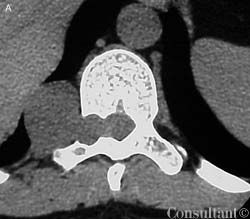

An otherwise healthy 34-year-old man presented with lower thoracic and right flank pain that followed a T10 dermatomal pattern. The axial CT image at the level of T10 seen here showed a soft tissue mass widening the neural foramen on the right and extending in a paraspinal location. The pathologic diagnosis of the resected mass was slow-growing fusiform neurofibroma without the plexiform changes frequently seen in type 1 neurofibromatosis, the hallmark lesions of which are caf au lait macules and multiple firm, subcutaneous neurofibromas.

Image courtesy of Will Beringer, DO.